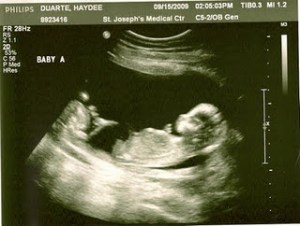

Here is the proof, in case you were wondering if we were pulling your leg or joking (as many do, when we share the news)! Have I mentioned that we don’t want to know the sex of the babies? We both think it will be a lot more fun to be surprised when they are born. So, in this case especially it was really nice to find out that the way the doctors keep track of both babies during my checkups is by calling them ‘Baby A’ and ‘Baby B’ — and they will be tracked like that throughout my entire pregnancy, so they will be able to monitor each baby’s growth and progress separately.

The pictures above were really fun. It was really the first time I could see them so clearly, instead of just looking at two little fuzzballs on the screen. I was shocked to see them positioned with their feet towards each other, but my doctor says they will do a whole lot more moving around before I deliver them. Although both of them wriggled around a lot during the ultrasound, Baby B was especially active–kicking and stretching its arms. So cute!

I hope you enjoyed your first glimpse at my little bundles of joy. I am bracing myself for a lot of kicking in the future. These days I just feel a few flutters here and there, so I can imagine how active they’ll both be as they grow bigger in my tummy.